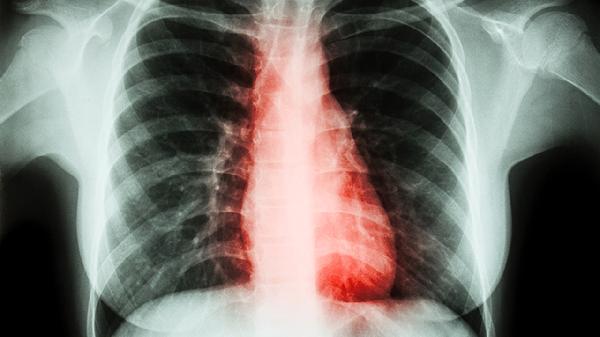

去肺火的药主要有清肺抑火片、羚羊清肺丸、养阴清肺口服液、牛黄清肺散、川贝枇杷露等。肺火多由外感热邪或内伤积热引起,表现为咳嗽、咽痛、痰黄黏稠等症状,需在医生指导下辨证用药。

肺火患者除药物治疗外,宜保持室内空气湿润,每日饮用梨汁、白萝卜汤等清热生津饮品。避免熬夜及辛辣刺激饮食,慢性咳嗽超过两周或出现咯血、胸痛时应及时复查胸部CT。用药期间若出现腹泻、皮疹等不良反应需立即停药并就医,不可自行调整中西药联合用药方案。